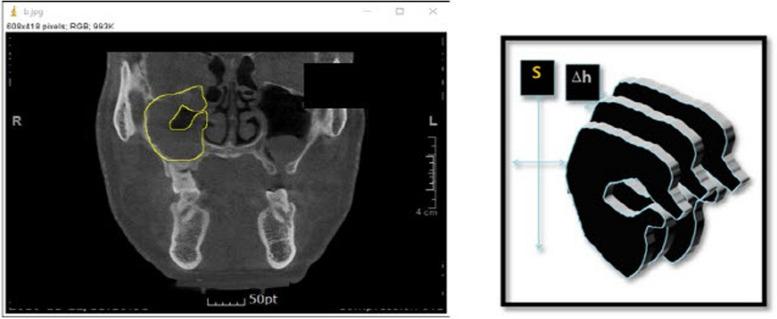

Odontogenic maxillary sinusitis (OMS) is widely acknowledged in both the dentistry and otolaryngology fields. Recently, iatrogenic odontogenic maxillary sinusitis cases can be encountered frequently. The purpose of this study was to evaluate the effect of intraoral sinus irrigation using the small lateral window approach in patients with odontogenic maxillary sinusitis by comparing pre- and postoperative volumetric measurement of CBCT and symptoms. We surveyed 21 patients who visited the Oral and Maxillofacial Surgery Department at PNUDH from 2016 to 2022. All the patients' information was extracted from an electronic database. The patients with a follow-up period of 2 months or more were included. The three-dimensional volumetric measurement was performed using the ImageJ program (National Institute of Health, University of Wisconsin).

Among 21 patients, 16 (76.1%) were male, and 5 (23%) were female. The most common type of surgery was general anesthesia (16 cases) in which oroantral fistula was present in 7 cases. In the causes of maxillary sinusitis, there were seven implant-related patients, five patients of tooth extraction, seven patients of bone grafting, and two patients in other groups. Radiographic opacity decreased by 40.15% after sinus irrigation especially in bone graft and tooth extraction cases. Clinically, symptoms improved in 17 patients (80.9%).

牙源性上颌窦炎(OMS)在牙科和耳鼻喉科领域都广为人知。近年来,医源性牙源性上颌窦炎病例屡见不鲜。本研究的目的是通过比较锥形束计算机断层扫描(CBCT)术前和术后的容积测量及症状,评估经口小外侧窗入路鼻窦冲洗术对牙源性上颌窦炎患者的疗效。我们调查了2016年至2022年期间在PNUDH口腔颌面外科就诊的21例患者。所有患者的信息均从电子数据库中提取。纳入随访期为2个月或更长时间的患者。使用ImageJ程序(美国国立卫生研究院,威斯康星大学)进行三维容积测量。

21例患者中,男性16例(76.1%),女性5例(23%)。最常见的手术类型是全身麻醉(16例),其中7例存在口腔上颌窦瘘。在上颌窦炎的病因中,有7例与种植相关,5例拔牙患者,7例骨移植患者,其他组2例。鼻窦冲洗后影像学上的不透光区减少了40.15%,尤其是在骨移植和拔牙病例中。临床上,17例患者(80.9%)症状改善。